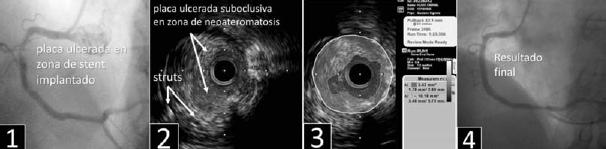

Método: paciente de 79 años, sexo masculino, con antecedentes de DM tipo II y tabaquista. Consultó por dolor retroesternal de tipo opresivo irradiado a cuello y elementos neurovegetativos. En el ECG se observó supradesnivel del ST (7 mm) anterolateral. Se derivó a CACG a las 3 h de iniciado el evento.

Resultado: en la CACG se observó la ADA ocluida en su tercio medio y una lesión del TCI de difícil estadificación y morfología atípica (figura 1). Se predilató la lesión y posteriormente se implanta stent sobre la lesión oclusiva. Se completa la valoración mediante el uso de IVUS en donde se observa una lesión moderada del TCI de aspecto ulcerado en su tercio medio (figura 2). A continuación se realizó ATC de dicha lesión con implante de stent (figura 3). El paciente presentó buena evolución clínica. Cumple prevención secundaria.

Conclusión: hay situaciones en la que la angiografía convencional encuentra limitaciones para definir las características morfológicas y la severidad de una lesión. El uso de IVUS clarifica estas características, guía en el tratamiento y logra una optimización de la técnica de ATC con stent.